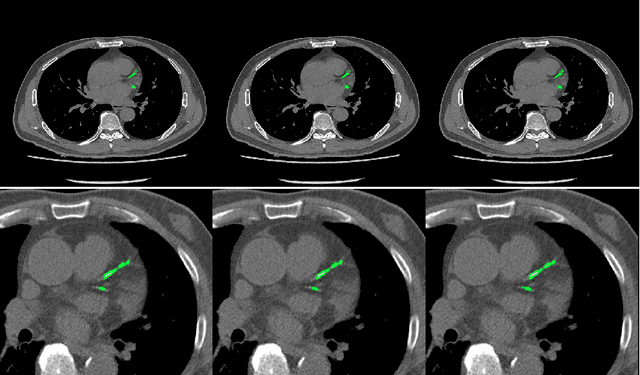

Abstract:Early diagnosis of pulmonary nodules (PNs) can improve the survival rate of patients and yet is a challenging task for radiologists due to the image noise and artifacts in computed tomography (CT) images. In this paper, we propose a novel and effective abnormality detector implementing the attention mechanism and group convolution on 3D single-shot detector (SSD) called group-attention SSD (GA-SSD). We find that group convolution is effective in extracting rich context information between continuous slices, and attention network can learn the target features automatically. We collected a large-scale dataset that contained 4146 CT scans with annotations of varying types and sizes of PNs (even PNs smaller than 3mm were annotated). To the best of our knowledge, this dataset is the largest cohort with relatively complete annotations for PNs detection. Our experimental results show that the proposed group-attention SSD outperforms the classic SSD framework as well as the state-of-the-art 3DCNN, especially on some challenging lesion types.